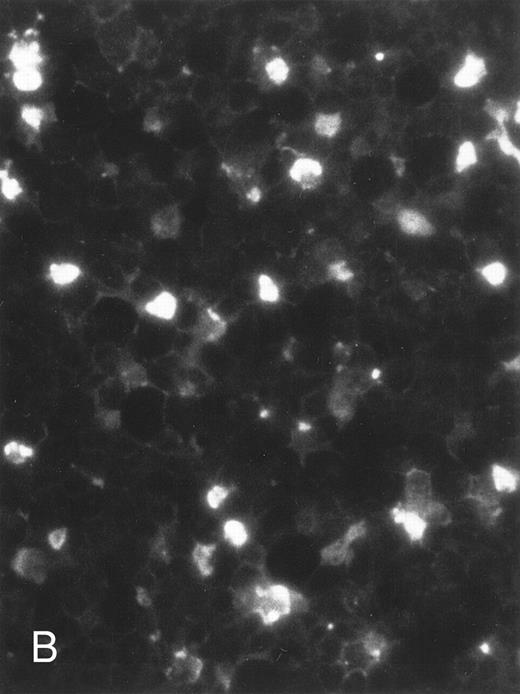

The apoptosis-specific genomic DNA cleavage was also assessed by the TUNEL (TdT-mediated dUTP nick end labelling) assay (In situ Cell Death Detection Kit, AP; Boehringer Mannheim). PLB-985 cells were treated with 10−6 mol/L 9-cis-RA for 3 days and assayed for DNA strand breakage. Control cells growing exponentially showed very limited fluorescent labeling, whereas RA-treated cells showed numerous positive cells (Fig 4). These results confirmed that RA induced specific DNA strand breakage in PLB-985 cells, indicative of the apoptotic process.

Induction of genomic DNA-nicking in apoptotic PLB-985 cells treated with 10−6 mol/L 9-cis-RA for 3 days. Cytospins were prepared from (A) normal and (B) RA-treated cells, and the TUNEL assay was performed, labeling the apoptosis-specific DNA strand breaks with fluorescent label as described in Materials and Methods.